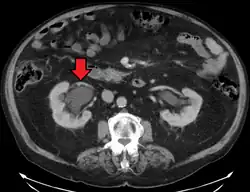

Hydronephrosis due to a kidney stone at the ureteral vesicular junction seen on CT scan

The choice of imaging depends on the clinical presentation (history, symptoms and examination findings). In the case of renal colic (one sided loin pain usually accompanied by a trace of blood in the urine) the initial investigation is usually a spiral or helical CT scan. This has the advantage of showing whether there is any obstruction of flow of urine causing hydronephrosis as well as demonstrating the function of the other kidney. Many stones are not visible on plain X-ray or IVU but 99% of stones are visible on CT and therefore CT is becoming a common choice of initial investigation. CT is not used, however, when there is a reason to avoid radiation exposure, e.g. in pregnancy.[13][14]